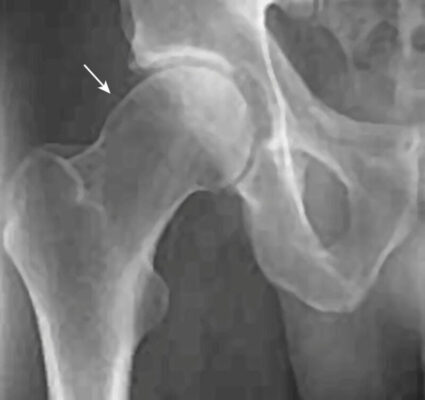

Dấu hiệu X quang cơ bản của FAI loại chỏm là giảm khoảng cách rìa xiên cổ – chỏm xương đùi ở phía trước hoặc trên, làm cho điểm nối cổ – chỏm xương đùi có vẻ phẳng hoặc lồi thay vì lõm. Đặc điểm này thường được gọi là biến dạng tay cầm súng lục.

“pistol grip”)